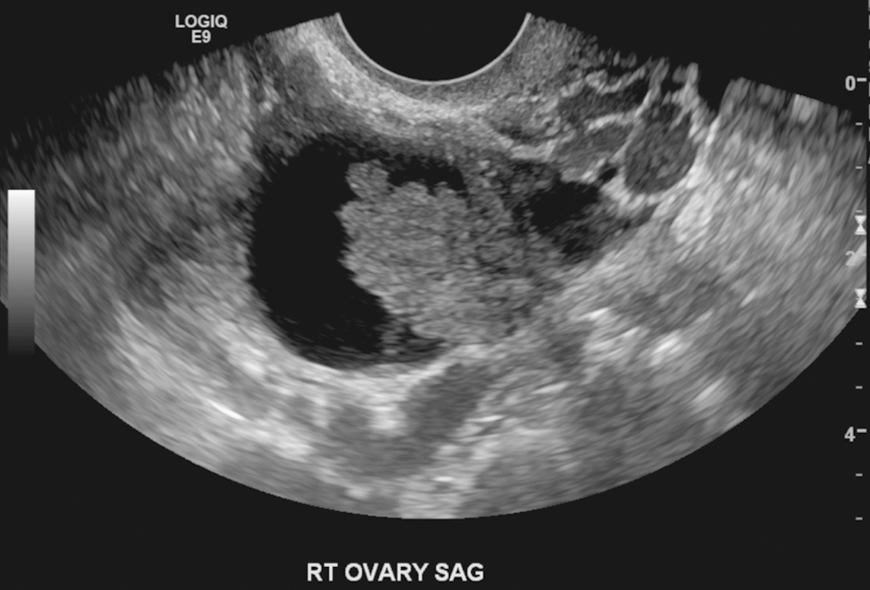

Le scanner abdominal retrouve une ascite importante associée à des nodules de carcinose péritonéale diffus et une masse pelvienne. Il n’existe pas de niveau jonctionnel sur le scanner mais un iléus reflexe important. Vous réalisez une échographie pelvienne qui retrouve cette image semblant être d’origine annexielle. Source : S. Khiat.

Question 12 - Quels critères échographiques en faveur d’une origine organique relevez-vous ?

Il convient de différencier les lésions ovariennes selon différents critères afin d’orienter vers une origine fonctionnelle (évolution kystique d’un follicule mature) ou organique (développé aux dépens d’un certain type cellulaire constituant le stroma ovarien).

En 2008, les auteurs du groupe IOTA (International Ovarian Tumor Analysis) ont publié des « règles simples » de l’évaluation endovaginale du kyste ovarien.

Cinq critères en faveur de la « malignité » : – tumeur solide irrégulière ; – présence d’un épanchement péritonéal ; – présence d’au moins quatre végétations ; – tumeur irrégulière multi-cloisonnée solide dont un des diamètres est supérieur à 10 cm ; – score colorimétrique fort en Doppler couleur.

Cinq critères en faveur de la « bénignité » : – kyste uniloculaire ; – présence de composantes solides dont le plus grand diamètre est inférieur à 7 mm ; – cône d’ombre ; – masse multiloculaire lisse avec un diamètre maximal inférieur à 100 mm ; – absence de flux en Doppler couleur. Source : S. Khiat.